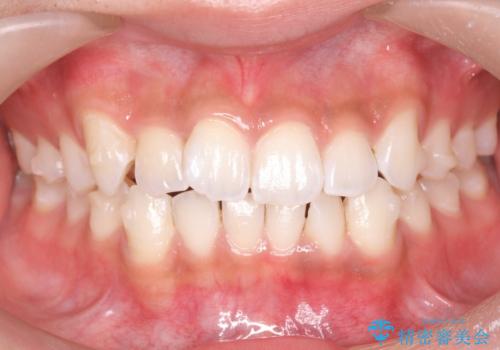

前歯のがたつき 1年かからず治療 マウスピース矯正

- 前歯のがたつきを主訴に来院。

インビザラインで歯を抜かずに並べました。

マウスピースの延長(リファインメント)もなく、短期間で綺麗に並びました。